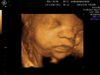

3d ultralyd av jenta vår i dag. 29 +1.

Sur dame som mente det var jo alt for sent til å få ok bilder nå! Dette var det beste og eneste jeg fikk. ( er ikke en utvekst på hodet der altså)

Men må innrømme jeg er skuffa når jeg ser hvor fine bilder dere andre har fått i samme uka... :-/